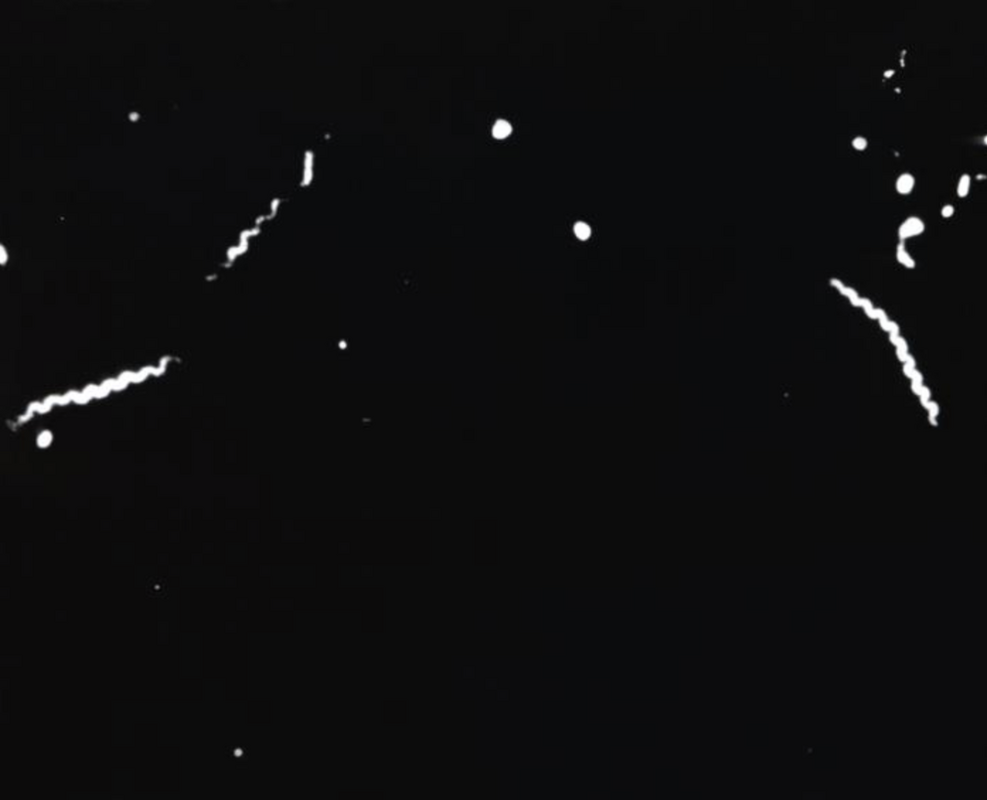

Только вскоре после начала XX века немецкий зоолог Фриц Шаудинн и дерматолог Эрих Хоффман впервые обнаружили этиологический агент заболевания - Treponema pallidum - в тканях больных. После идентификации T. pallidum ученые знали, на что следует обратить внимание при разработке тестов для диагностики сифилиса. Ниже представлено фото спирохет T. pallidum в инфицированной ткани яичка, окрашенных серебром модифицированным методом Штайнера. Возможно, это не совсем то, что видели Шаудинн и Хоффман, но это хороший пример того, как ткань может быть инфицирована большим количеством спирохет при исследовании под микроскопом.

Спирохеты Treponema pallidum в образце ткани яичек кролика, приготовленном с использованием модифицированного метода окрашивания серебром по Штайнеру.

Трепонемы также могут быть обнаружены в образцах, собранных с неоральных поражений слизистой оболочки и кондилом. Образцы выделений из носа у новорожденных с сифилитическим ринитом, собранные у больных врожденным сифилисом, часто изобилуют трепонемами, которые также легко визуализируются с помощью микроскопии в темном поле. В шапке статьи представлено фото, сделанное с использованием техники визуализации в темном поле, демонстрирующая наличие спирохет T. pallidum.